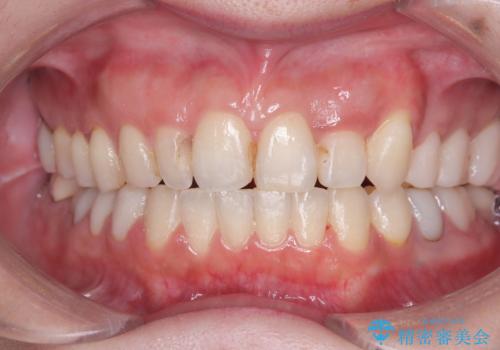

八重歯と正中のズレを解消!目立ちにくいワイヤー矯正で美しい歯並びへ

担当医 河口智英